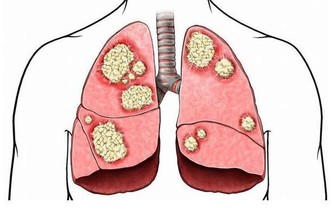

酒精在人體的代謝物——乙醛,攝入量過多,攝入時間過長,必會在人體囤積增加,繼而對許多組織和器官,特別是肝臟,造成極大傷害(進程如圖所示)!

肝怕“1水”,腎怕“1字”,胃怕“3事”! 勸你一個都別沾,別等熬成癌才後悔

如果將不同的酒混著喝,如白酒和啤酒,還會加速酒精在全身的滲透作用,使血液中的酒精濃度在短時間內急速增加,對肝臟損害更大。